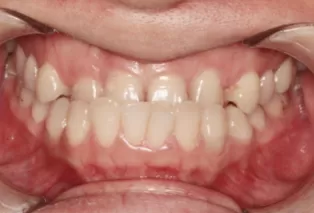

Photos intra-orales